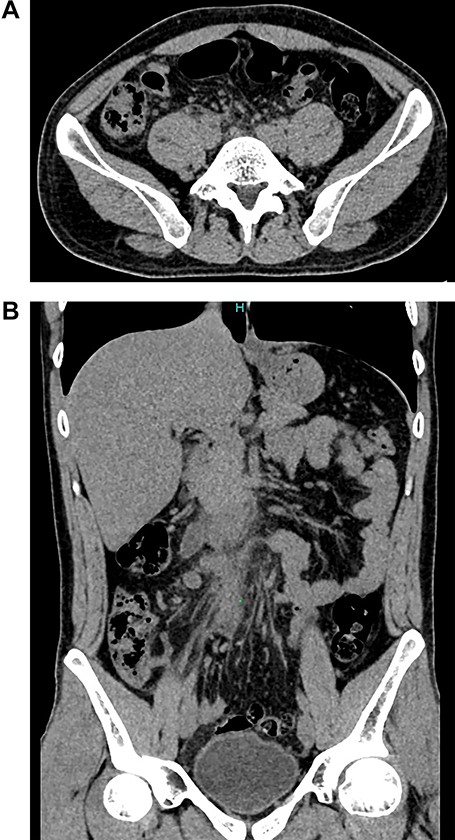

Patient is a 32-year-old male without past medical history, he presented to the emergency room with a 5-day history of intermittent abdominal pain in his upper abdomen. At first, his pain was colicky and mild, nonetheless, as the days went by, the pain became much more severe and migrated to his lower right abdomen. On clinical examination, a febrile and dehydrated patient was encountered, his abdomen was very sensitive to gentle pressure and there was severe pain on sudden release of deep pressure in his lower right abdomen. Complementary exams revealed leukocytosis with neutrophilia and an elevated C reactive protein, computed tomography (CT) revealed slight inflammation of the surrounding retroperitoneal fat around the appendix (Fig. 1A and B). Acute abdomen due to appendicitis was suspected and surgery was decided. At surgery, on gross examination, the appendix measured 6 cm in length and 0.7 cm in diameter. The external surface of the appendix had a pink color with gray patches and showed congestion, no lymph nodes or other masses were found thus appendectomy was completed without complications.

(A) CT, slight enhancement of the retroperitoneal fat. (B) CT, the appendix is seen with surrounded by retroperitoneum fat.